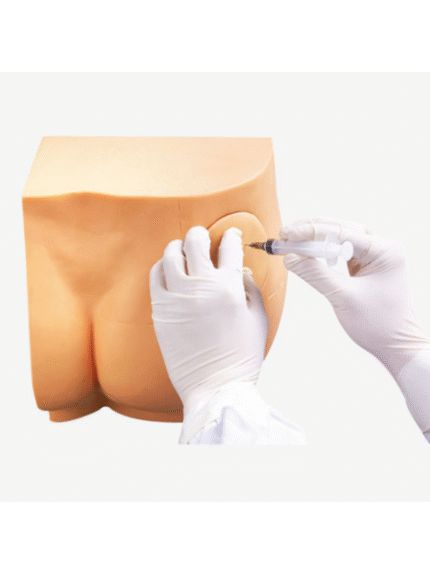

ATL-111 BUTTOCKS INTRAMUSCULAR INJECTION SIMULATOR SOFT